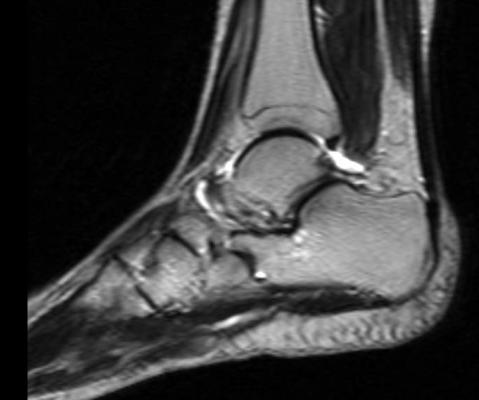

September 6, 2017 — A new study by the Harvey L. Neiman Health Policy Institute found that in the Medicare population, the utilization rates have increased in both volume and per beneficiary over the past two decades for the most common musculoskeletal (MSK) extremity imaging modalities. The study focused on radiography, magnetic resonance imaging (MRI), computed tomography (CT) and ultrasound.

Gyftopoulos and his colleagues used billing data obtained from Centers for Medicare and Medicaid Services (CMS) Medicare Physician Supplier Procedure Summary Master Files from 1994 to 2013. The Neiman Imaging Types of Service (NITOS) radiology claims classification system was used to identify those HCPS codes corresponding with non-vascular extremity imaging. The following increases in MSK extremity imaging were found over the past two decades: 43 percent for radiography, 619 percent for MRI, 754 percent for CT and 528 percent for ultrasound.